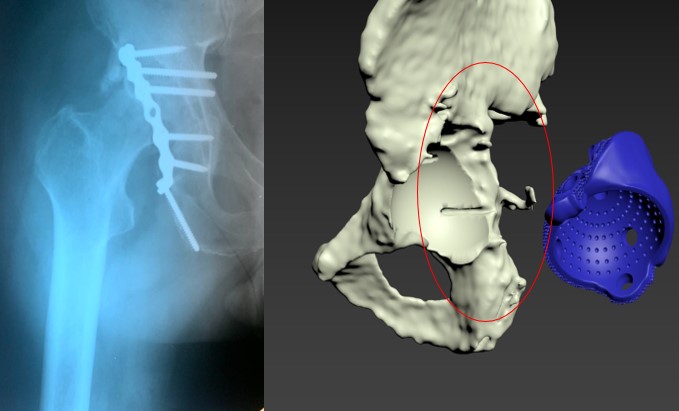

Етапи проектування індивідуальних аугументів для ревізійного ендопротезування колінного суглоба

Пацієнт С-к Роман Михайлович, 1975 рік. Травма в результаті ДТП (7.10.2023 р.) – перелом заднього краю лівої кульшової западини зі зміщенням. Післятравматичний лівобічний коксартроз 4 ст., стан після МОС заднього краю лівої кульшової западини пластиною та гвинтами. Згинально-привідна контрактура зліва. Наслідки ушкодження лівого сідничного нерва в лівій сідничній ділянці. Стан після встановлення ЕСС “НейСі-3М” на малогомілковий (CPN) та великогомілковий (TN) нерви в н/3 лівого стегна.

Операція: Вилучення металофіксаотора. Повна артропластика лівого кульшового суглоба з індивідуальним ацетабулярним компонентом

Пацієнт С-к Роман Михайлович, 1975 рік. Травма в результаті ДТП (7.10.2023 р.) – перелом заднього краю лівої кульшової западини зі зміщенням.

Післятравматичний лівобічний коксартроз 4 ст., стан після МОС заднього краю лівої кульшової западини пластиною та гвинтами. Згинально-привідна контрактура зліва. Наслідки ушкодження лівого сідничного нерва в лівій сідничній ділянці. Стан після встановлення ЕСС “НейСі-3М” на малогомілковий (CPN) та великогомілковий (TN) нерви в н/3 лівого стегна.

Спроектована та імплантована індивідуальна, пориста, титанова, 3D-друкована кульшова западина, фіксована гвинтами.